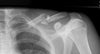

25

describe injury

comminuted, displaced, mid shaft clavicle fracture

26

complications of clavicle fracture

* non union * malunion * vascular injury * infection * skin tenting